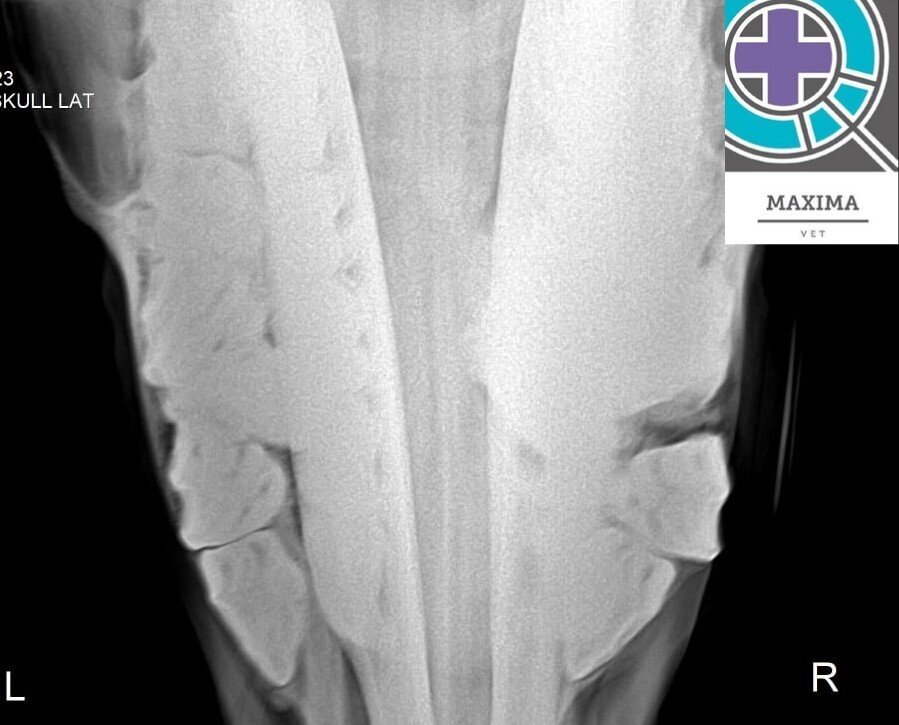

🟢MAXIMA VET: ОТВЕЧАЕМ на ВОПРОС нашей викторины. ПРАВИЛЬНЫЙ ОТВЕТ: ПОЛИОДОНТИЯ или сверхкомплект ЩЕЧНЫХ ЗУБОВ.

При осмотре у лошади справой стороны на верхней челюсти уплотнение, связанное с забиванием корма в диастеме.

При осмотре ротовой полости выявлена полиодонтия премоляров, редко встречающаяся патология. В литературе и нашей практике чаще встречаются случаи полиодонтии моляров.

При рентгенологическом обследовании премоляры смещены медиально с образованием диастемы. ВАЖНО: Будьте внимательны к вашей лошади, обращайте внимание на любое изменение в поведении. И помните, профилактика лучше, чем лечение.